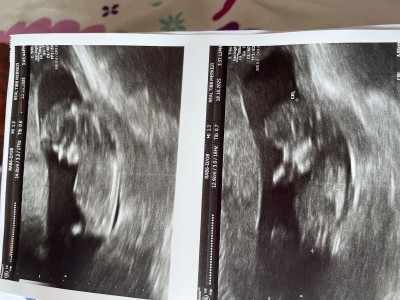

Doktor gordum ama soylemivem dedi tahminim var tam goremiyorum dedi o yuzden soylemedi

Gebelik haftası 11+6

Bir kizim var inse Allah buda erkek olur ama fotodan hic biwey anlamiyorum ayaklarini cekmemiw galiba

Bebek kendini göstermiyor olabilir zaten zor şimdi hani doktor görse bile yüzde 50 tahmini olarak şimdi erken 14 haftanizda giderseniz daha net olur hanımlar o erkeği nasıl gördü şaşırdım

Bazen goruyorum keseye gore tahminler yapiyorlar

Ben ultrason kâğıdın bakarak konuştum . Ölçüme göre değil tabi sadece tahmin bu çünkü bu ultrason kağıdında nub tam görülmüyor bacaklar kapali

Erkek bence canm ordan bişey çıkmış çünkü 😊

Kesinlikle kız bebek bu iki çizgi var öğrenince yaz bak kesinlikle kız

Nub kısmına bak anlarsın